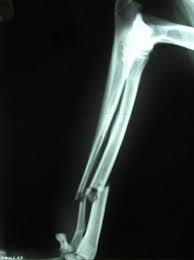

1) Fraktura is simple: If a bone is cracked not until injuring other organs around it, such as the organ muscles.

2) complex or compound Fraktura fraktura: if broken bone causes the muscles and the skin is injured, even a broken tip could be sticking it out.

3) greenstick: Fraktura if cracked or broken bones are not to separate the bone into two parts.

4) Fraktura comminuted or crumbles: If a bone is cracked into pieces but still stuck inside the muscle.